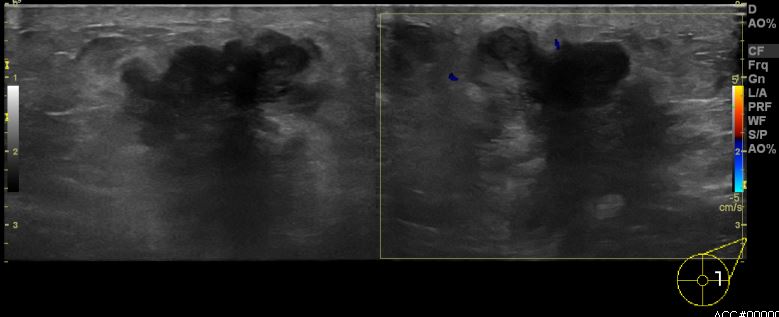

상기환자 좌측에 만져지는 멍울로 내원하신 50대 여성분으로 좌측 만져지는 멍울

중심핵생검 시행하여 좌측 침윤성 유관암 진단 되었습니다.